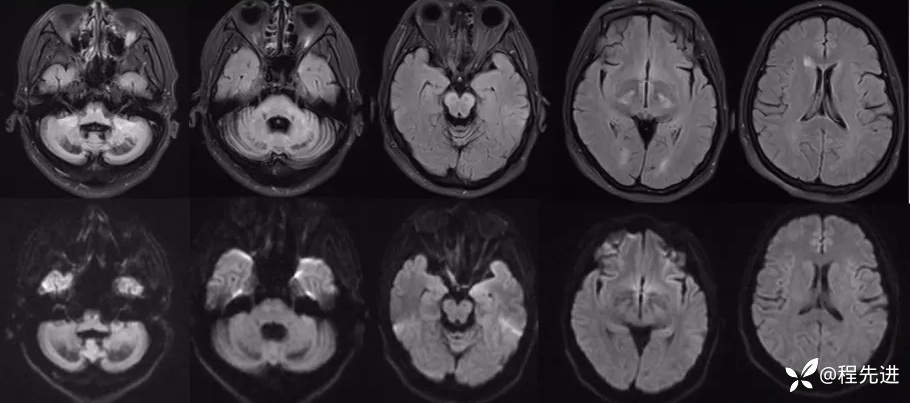

FLAIR: